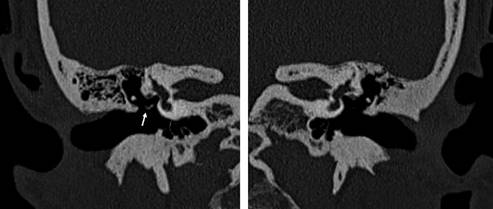

Femenino de 22 años con hipoacusia conductiva en oído izquierdo de más de 10 años de evolución. A la exploración física y la otoscopia: pabellones auriculares y membranas timpánicas normales; prueba de Rinne positiva en OD derecho y negativa en OI; prueba de Weber lateralizada a OI. la audiometría tonal entre 20-40 dB, mayor en frecuencias graves y con presencia de la muesca de Carhart a los 2000 Hz en la vía ósea ipsilateral; la impedanciometría con reflejos ipsi y contralaterales con estímulo de 100 dB mostró curvas timpanométricas normales y reflejos ipsilaterales y contralaterales ausentes en OI e ipsilaterales positivos y contralaterales ausentes en OD derecho. La tomografía computarizada mostró agenesia del proceso largo del yunque y del estribo izquierdo, sin cruras, presente la platina (Figuras 1 y 2).

Figura 1: Tomografía computarizada de oídos con reconstrucción coronal, en el lado derecho se aprecia al proceso largo del yunque, la articulación incudoestapedial y al estribo en la ventana oval (flecha); en el lado izquierdo existe agenesia de estas estructuras.